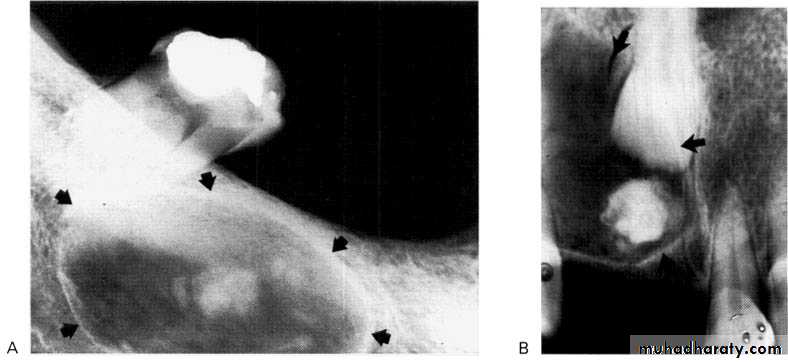

Adenomatoid Odontogenic Tumour (AOT

• Site: Anterior maxilla — incisor/canine region, occasionally anterior mandible.• Shape: — Monolocular

— Round or oval — Often surrounds an entire unerupted tooth.

• Outline: — Smooth and well defined

— Well corticated.

Radiodensity: — Initially radiolucent, but small opacities (snow flakes) within the central radiolucency may be seen peripherally as the lesion matures.

Calcifying Odontogenic Cyst (Gorlin Cyst)

It presents typically as a radiolucency resembling other odontogenic cysts, but, as it develops, a variable amount of calcified material becomes evident, scattered throughout the radiolucency. The opacities can range from small flecks to large masses.

Shape: Variable, but usually monolocular.

Outline: — Smooth, well defined

— Often corticated.

Radiodensity: — Initially radiolucent but in more advanced stages contains a variable amount of calcified radiopaque material of tooth-like density.